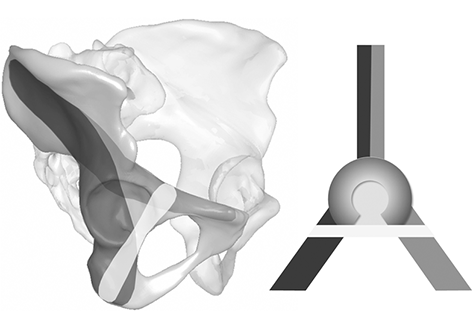

This computer-aided 3-D radiomorphometric study examined 124 CT Digital Imaging and Communications in Medicine (DICOM) datasets of intact human pelves (248 acetabula) to visualize the spatial IA corridors as the sum of all intraosseous screw positions. DICOM files were pre-processed using the Amira® 4.2 visualization software. Final corridor computation was accomplished using a custom-made software algorithm. The volumetric measurement data of each corridor were calculated for further statistical analyses. Correlations between the volumetric values and the biometric data were investigated. Furthermore, the influence of hip dysplasia on the IA corridor configuration was analyzed.

The IA corridors consistently showed a double-cone shape with the isthmus located at the acetabular fovea. In 97% of male and 91% of female acetabula, a corridor for a 3.5-mm screw could be found. The number of IA corridors was significantly lower in females for screw diameters ≥ 4.5 mm. The mean 3.5-mm screw corridor volume was 16 cm3 in males and 9.2 cm3 in female pelves. Corridor volumes were significantly positively correlated with body height and weight and with the diameter of Köhler’s teardrop on standard AP pelvic X-rays. No correlation was observed between hip dysplasia and the IA corridor extent.

IA corridors are consistently smaller in females. However, 3.5-mm small fragment screws may still be used as the standard implant because sex-specific differences are significant only with screw diameters ≥ 4.5 mm. Congenital hip dysplasia does not affect secure IA screw insertion. The described method allows 3-D shape analyses with highly reliable results. The visualization of secure IA corridors may support the spatial awareness of surgeons. Volumetric data allow the reliable assessment of individual IA corridors using standard AP X-ray views, which aids preoperative planning.

The generated DICOM files were pre-processed semiautomatically by a custom-made C++ software algorithm implemented in the scientific visualization software Amira